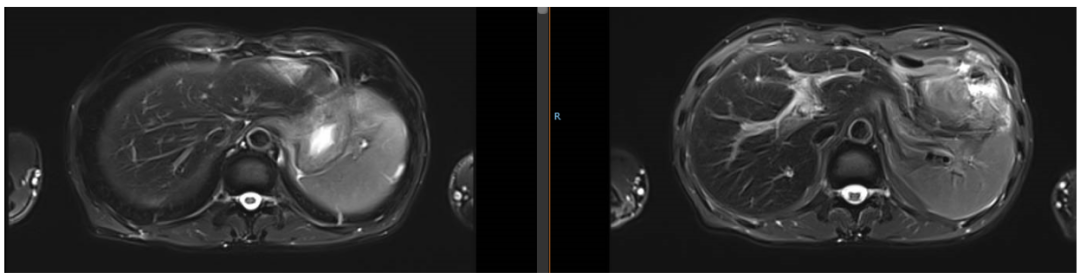

2019年1月24日,经4个周期赫赛汀+DF后,患者肝脏转移灶明显缩小。

2018年10月17日,化疗前

2019年1月24日,化疗后